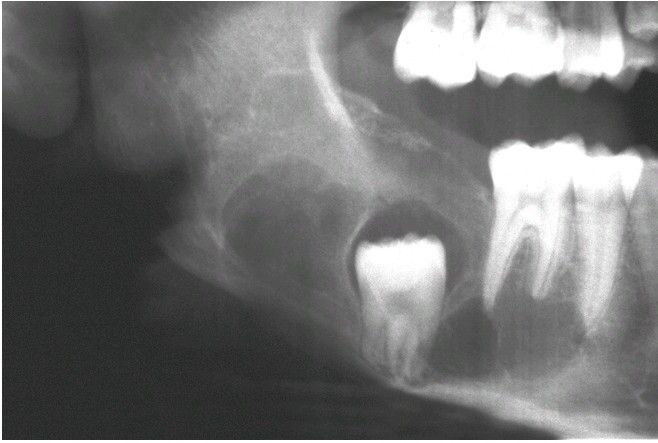

Ameloblastic Fibroma

Multilocular radiolucent defect associated with an unerupted second molar.